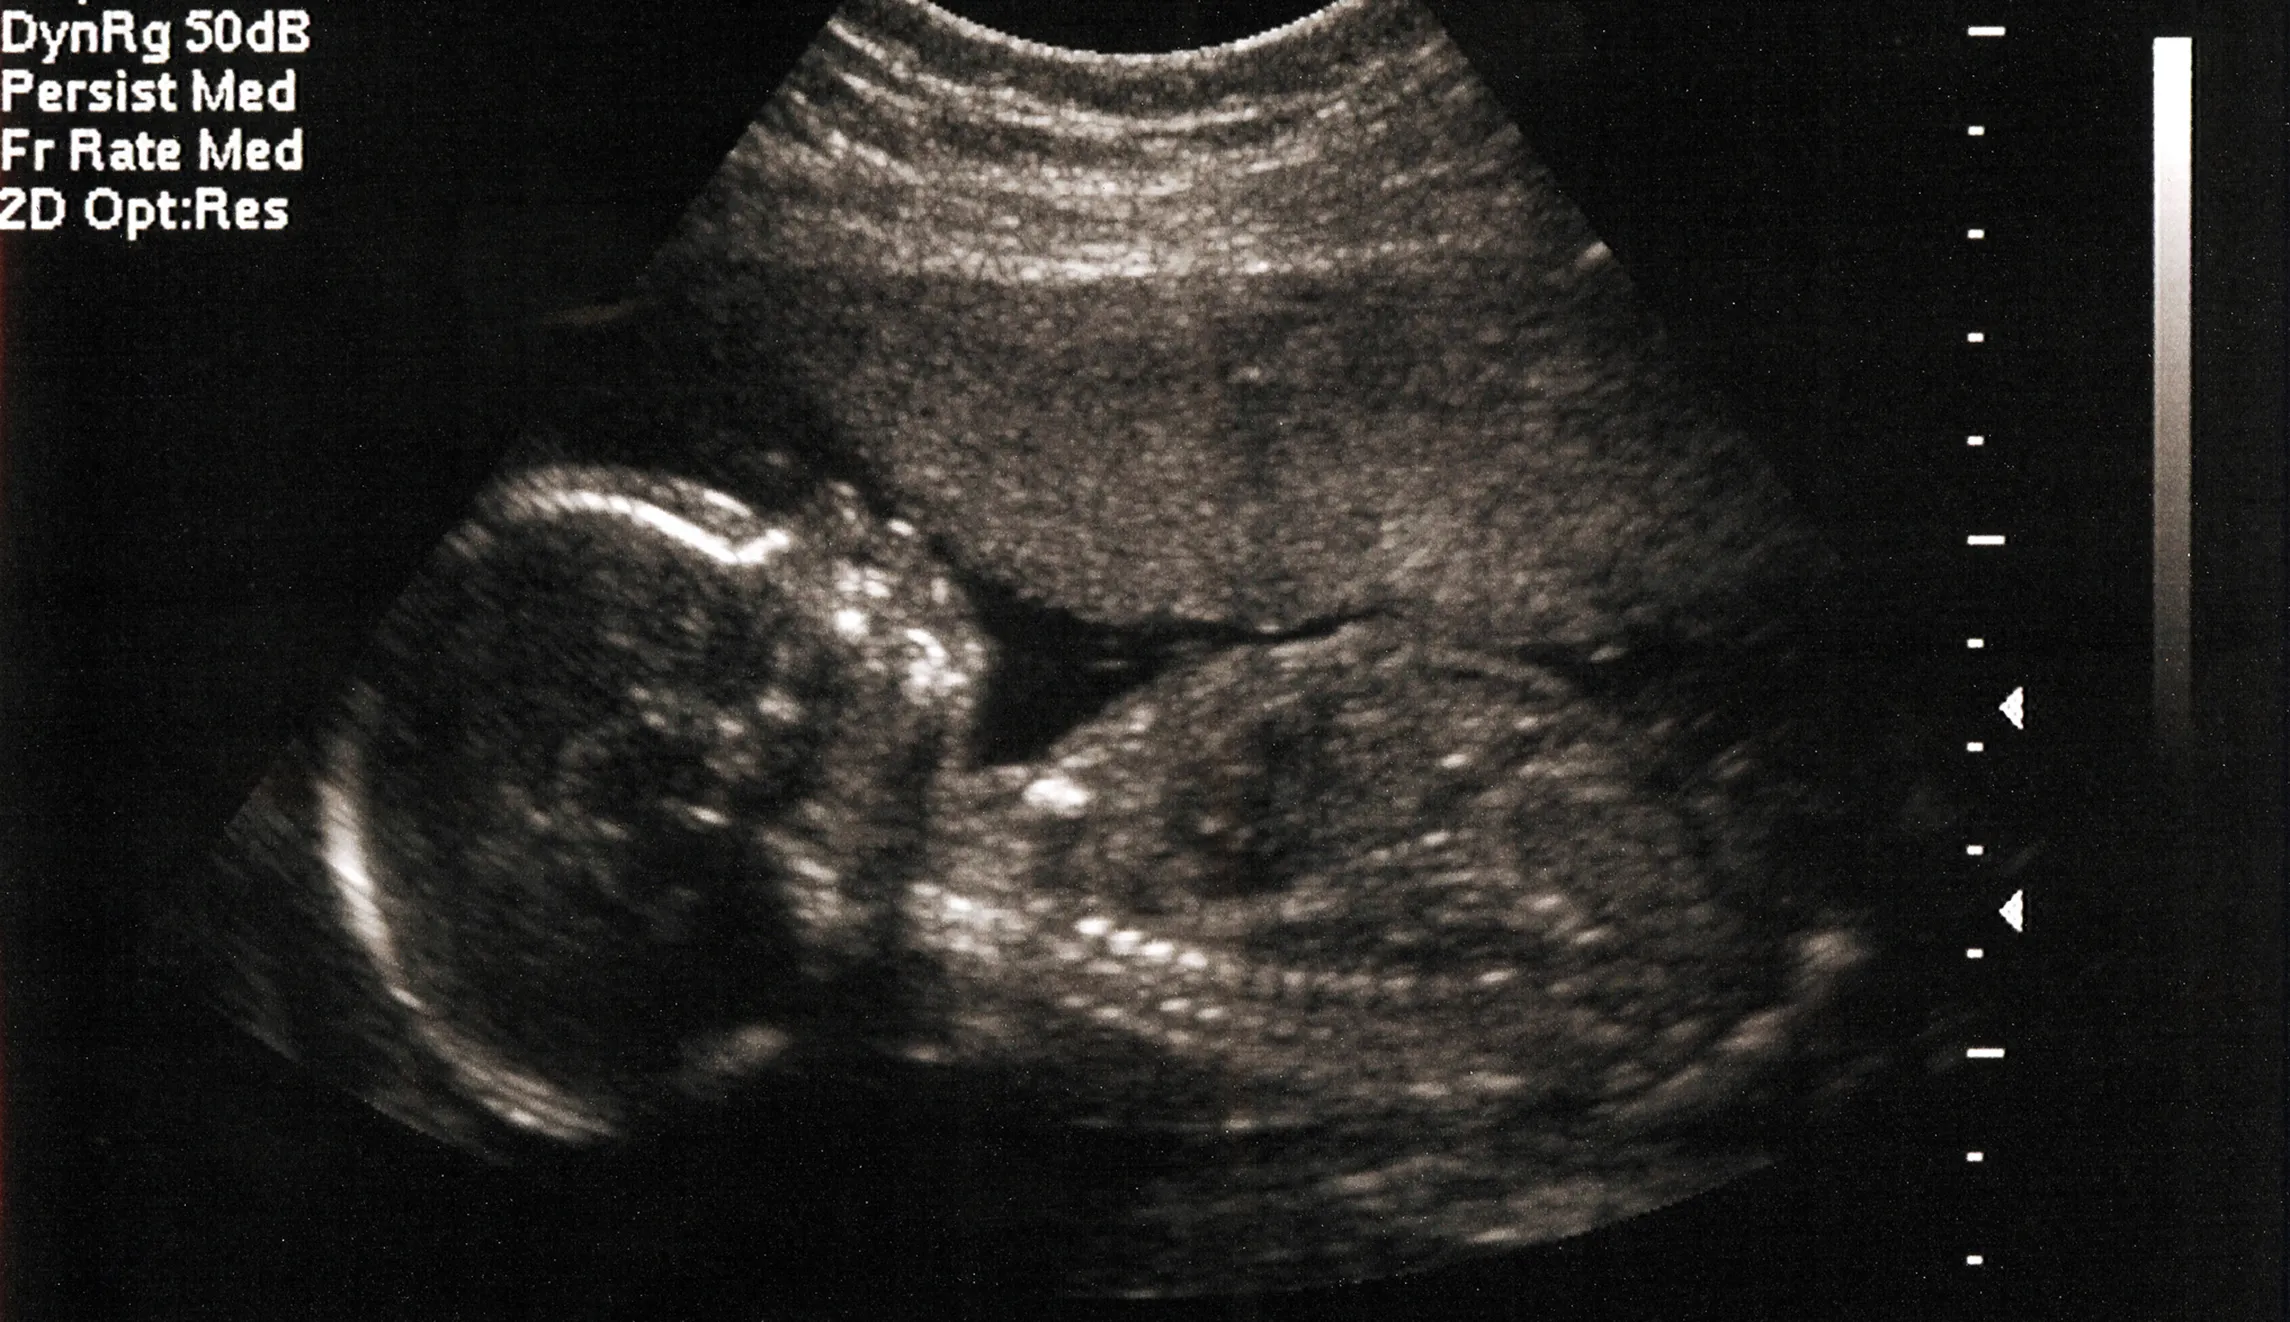

Texas lawmakers passed a bill last year that banned “dismemberment” abortions on a live baby. This is otherwise known as a dilation and evacuation (D & E) wherein a doctor pulls apart the baby’s limbs with a forceps or sopher clamp, and which usually occur in the second trimester, when the baby is too big to simply be suctioned out of the woman’s uterus.

Pro-life advocates and lawmakers in Texas have paved the way in demonstrating alternative methods to lowering abortions. One would imagine a trial demonstrating the gruesome and ghoulish details of one of the most common methods of abortions would have this effect as well. At the least, it laid bare one of the most common abortion myths: That a “fetus” is just a blob of tissue which needs to be discarded as such. If that were true, such effort to remove the baby, whether through injections which stop a baby’s heart or a D & E, would not be necessary. Perhaps this case will provide a landmark decision for other pro-life lawmakers, wrestling with how to save the lives of the unborn.